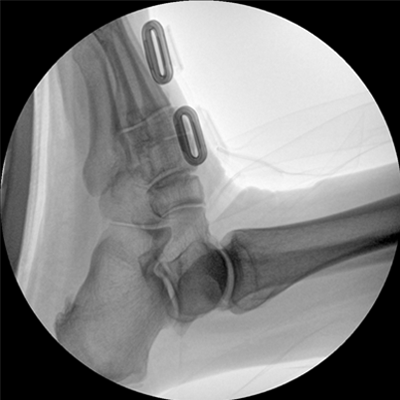

智能化控制系統(tǒng), 讓手術(shù)高效暢捷

四維電動(dòng)運(yùn)動(dòng)控制,平滑定位,使得復(fù)雜角度快速實(shí)現(xiàn)。

專業(yè)的圖像處理系統(tǒng),為您提供高分辨率、高灰階圖像。